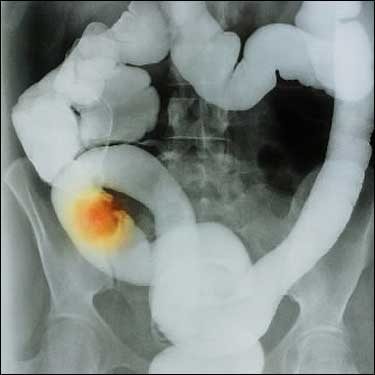

JH Silber et ses collègues ont cherché à analyser la nature et les causes de cette inégalité. Ils ont tenté de préciser si elle était le fait d’un mode de présentation ou d’une prise en charge thérapeutique différentes entre Blancs et Noirs. Ils ont également essayé de quantifier le rôle des facteurs socio-économiques et de voir la tendance évolutive en comparant 2 périodes allant de 1991 à 1995 et de 1999 à 2005. Les informations ont été tirées des banques de données informatisées de Medicare sur une période allant de 1991 à 2005. Au total 88 858 patients, âgés de 65 ans ou plus, chez qui un diagnostic de CC avait été porté récemment et avec un suivi minimum de 4 ans ont été identifiés. Ils ont été classés en fonction de l’ethnie (Noirs vs Blancs hispaniques ou non), de leurs comorbidités, des caractéristiques propres de la tumeur colique (stade, grade), du nombre de ganglions prélevés en peropératoire et du nombre de ganglions positifs, du risque calculé de récidive.

Un collectif de 7 677 patients noirs, âgés de 65 ans ou plus, dont le diagnostic de CC avait été porté entre 1991 et 2005 et le suivi assuré jusqu' au 3 Décembre 2009 a donc été apparié à 3 ensembles de patients blancs, de même effectif. On notait 25,2 % de diabétiques chez les Noirs face à 17,1 % chez les Blancs. Il a été également retrouvé des différences de prise en charge : 16,7 % des patients noirs n’ont pas eu de traitement actif vs 9,3 % des malades appariés blancs (p < 0,001) ; 14,7 % des Noirs ont reçu, en cas de chimiothérapie, une association comportant de la fluoropyrimidine face à 21,7 % des Blancs (p < 0,001). Le recours à une chimiothérapie adjuvante a été moins fréquent pour les Noirs (19,9 % vs 26,5 %, p < 0,001) ; 61,1 % des cancers chez les Noirs ont été traités par chirurgie exclusive vs 58,0 % chez les Blancs (p < 0,001).

A 5 ans, la différence absolue de survie entre les 2 populations s’établit globalement à 9,9 % (intervalle de confiance à 95 % [IC95] de 8,3 à 11,4 %, p < 0,001). Elle se maintient non modifiée entre 1991 et 2005. Après appariement en fonction du mode de présentation (caractéristiques tumorales, comorbidité..), elle passe de 9,9 % à 4,9 % (IC95 : 3,6- 6,1 %) tout en restant très significative (p < 0,001). L’appariement en fonction des modalités diverses de prise en charge la fait ressortir à 4,3 % (IC95 : 2,9- 5,5 % ; p < 0,001). On a pu calculer que les différences de traitement représentaient 0,6 % des 9,9 % de la disparité globale de survie à 5 ans. Quoique de façon non significative, la disparité globale de survie a augmenté au fil des années, passant de 8,5 % de 1991 à 1998 à 11,5 % entre 1999-2005 (Hazard Ratio, HR, de 1,10; IC95 : 0,98- 1,24; p = 0,093).

En fonction du stade du CC, les auteurs n’ont mis en évidence aucune différence de survie en cas de présentation stade I et II. En cas de stade IV, la survie a été naturellement plus courte dans les 2 populations, avec, là encore, un léger avantage mais significatif pour les Blancs. C’est dans les stades III que les différences en matière de traitement apparaissent les plus notables. Dans ce groupe, 3,3 % des patients noirs n’ont reçu aucun traitement vs 1,6 % des Blancs (p = 0,002). Moins de patients noirs ont eu un double traitement, associant chirurgie et chimiothérapie (42,11 % face à 55,0 % ; p < 0,001). La différence de survie à 5 ans est conséquente, 41,2 % vs 43,7 % (p = 0,013).